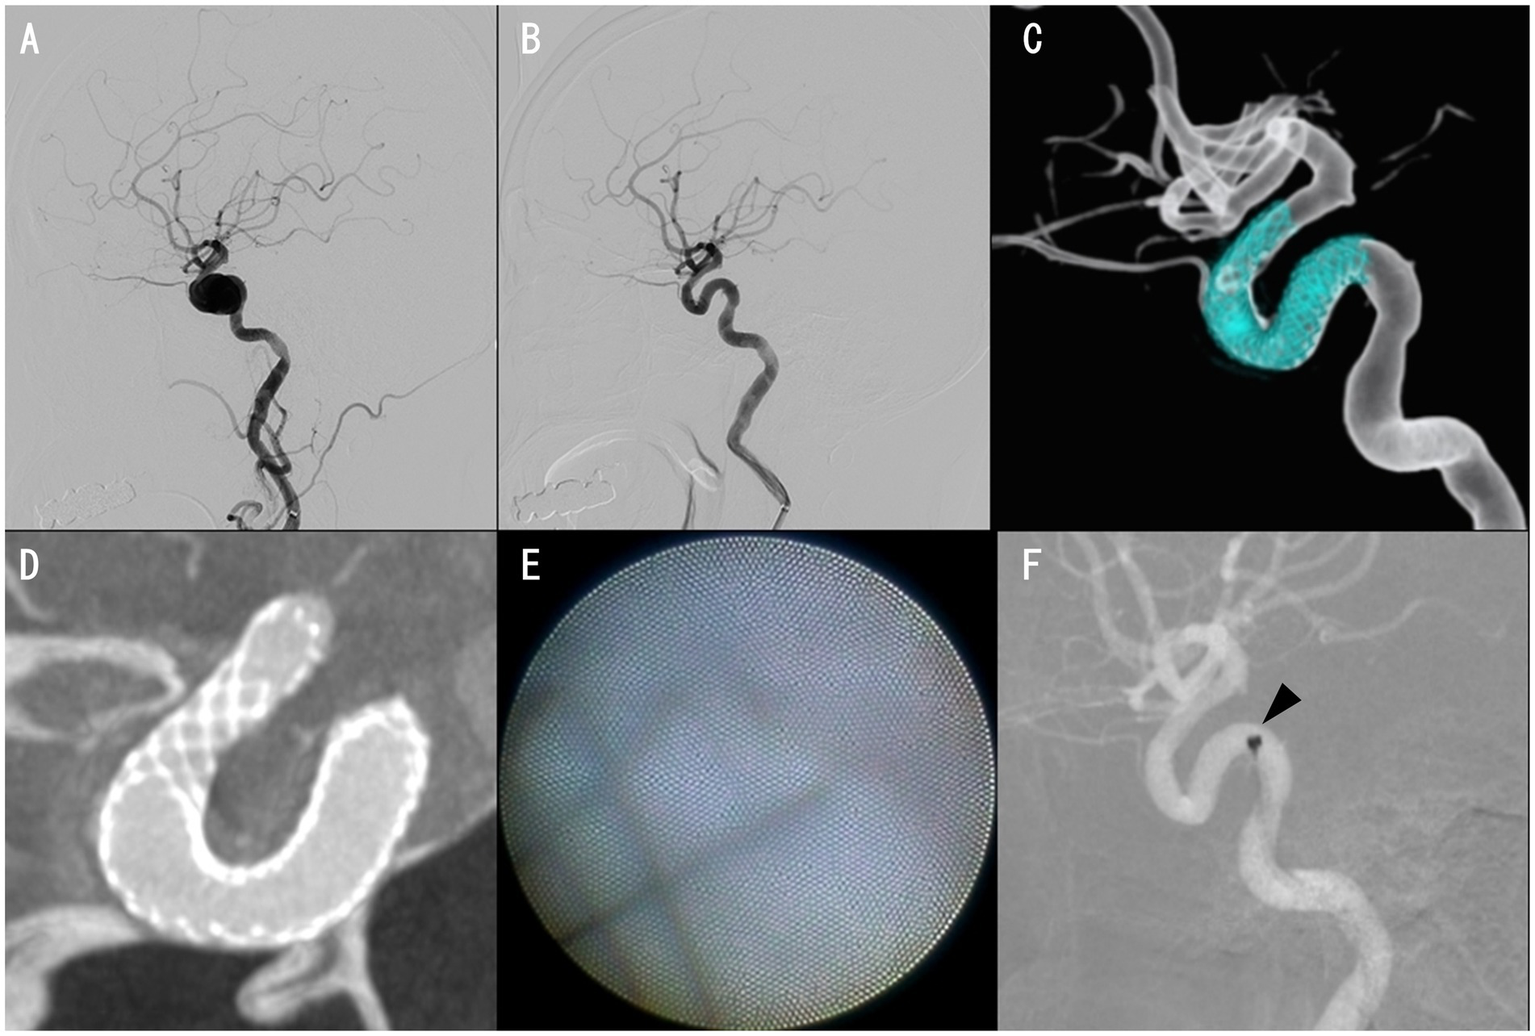

3.1 Representative case (case 8)

Case 8 was an 81-year-old woman. The PIPELINE Flex with Shield Technology was placed, followed by full-length percutaneous transluminal angioplasty for an asymptomatic unruptured cavernous ICA aneurysm with a maximum diameter of 13.8 mm (Figures 2A–C). Cone-beam CT with 20% diluted contrast did not display any radiolucent gap (Figure 2D), but the angioscopy revealed grade 1 neointima (Figures 2E, F). Based on these results, DAPT was terminated, and the regimen was continued on aspirin alone, with no ischemic events experienced by the patient over the following month.

Figure 2

Case 8 images. Preinterventional right internal carotid angiography (ICAG) displaying cavernous ICA aneurysm (A). The aneurysm was almost occluded, with only a small amount of blood flow near the neck in the right ICAG 6 months after placing a PIPELINE Flex with shield technology (B,C). Cone-beam CT with 20% diluted contrast exhibiting no apparent radiolucent gap (D). Proximal edge of the PIPELINE Flex covered with thin neointima (E). Angioscope position, where the image reflected in E was obtained (F, arrowhead).